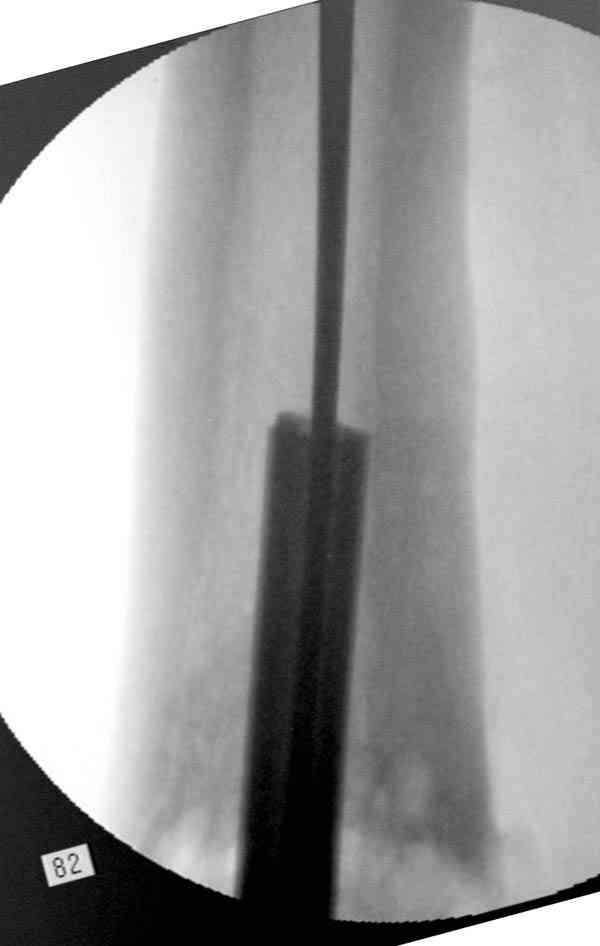

Периферический отломок стержня - наверно, надо воспользоваться отверстием, над ним сделать трепанацию и через него вверх провести длинную спицу, сделав на ее нижнем конце крючок. Лучше уже перед этим рассверлить центральный отломок.

Приспособление для удаления сломанных штифтов и наличие ЭОП облегчит задачу. При отсутствии крючка тогда можно применить обычный длинный ball pointed guide wire от интрамедулярного набора. Проволока, пропущенная за пределы гвоздя и зажатая другая вытащат сломанный конец штифта без проблем.